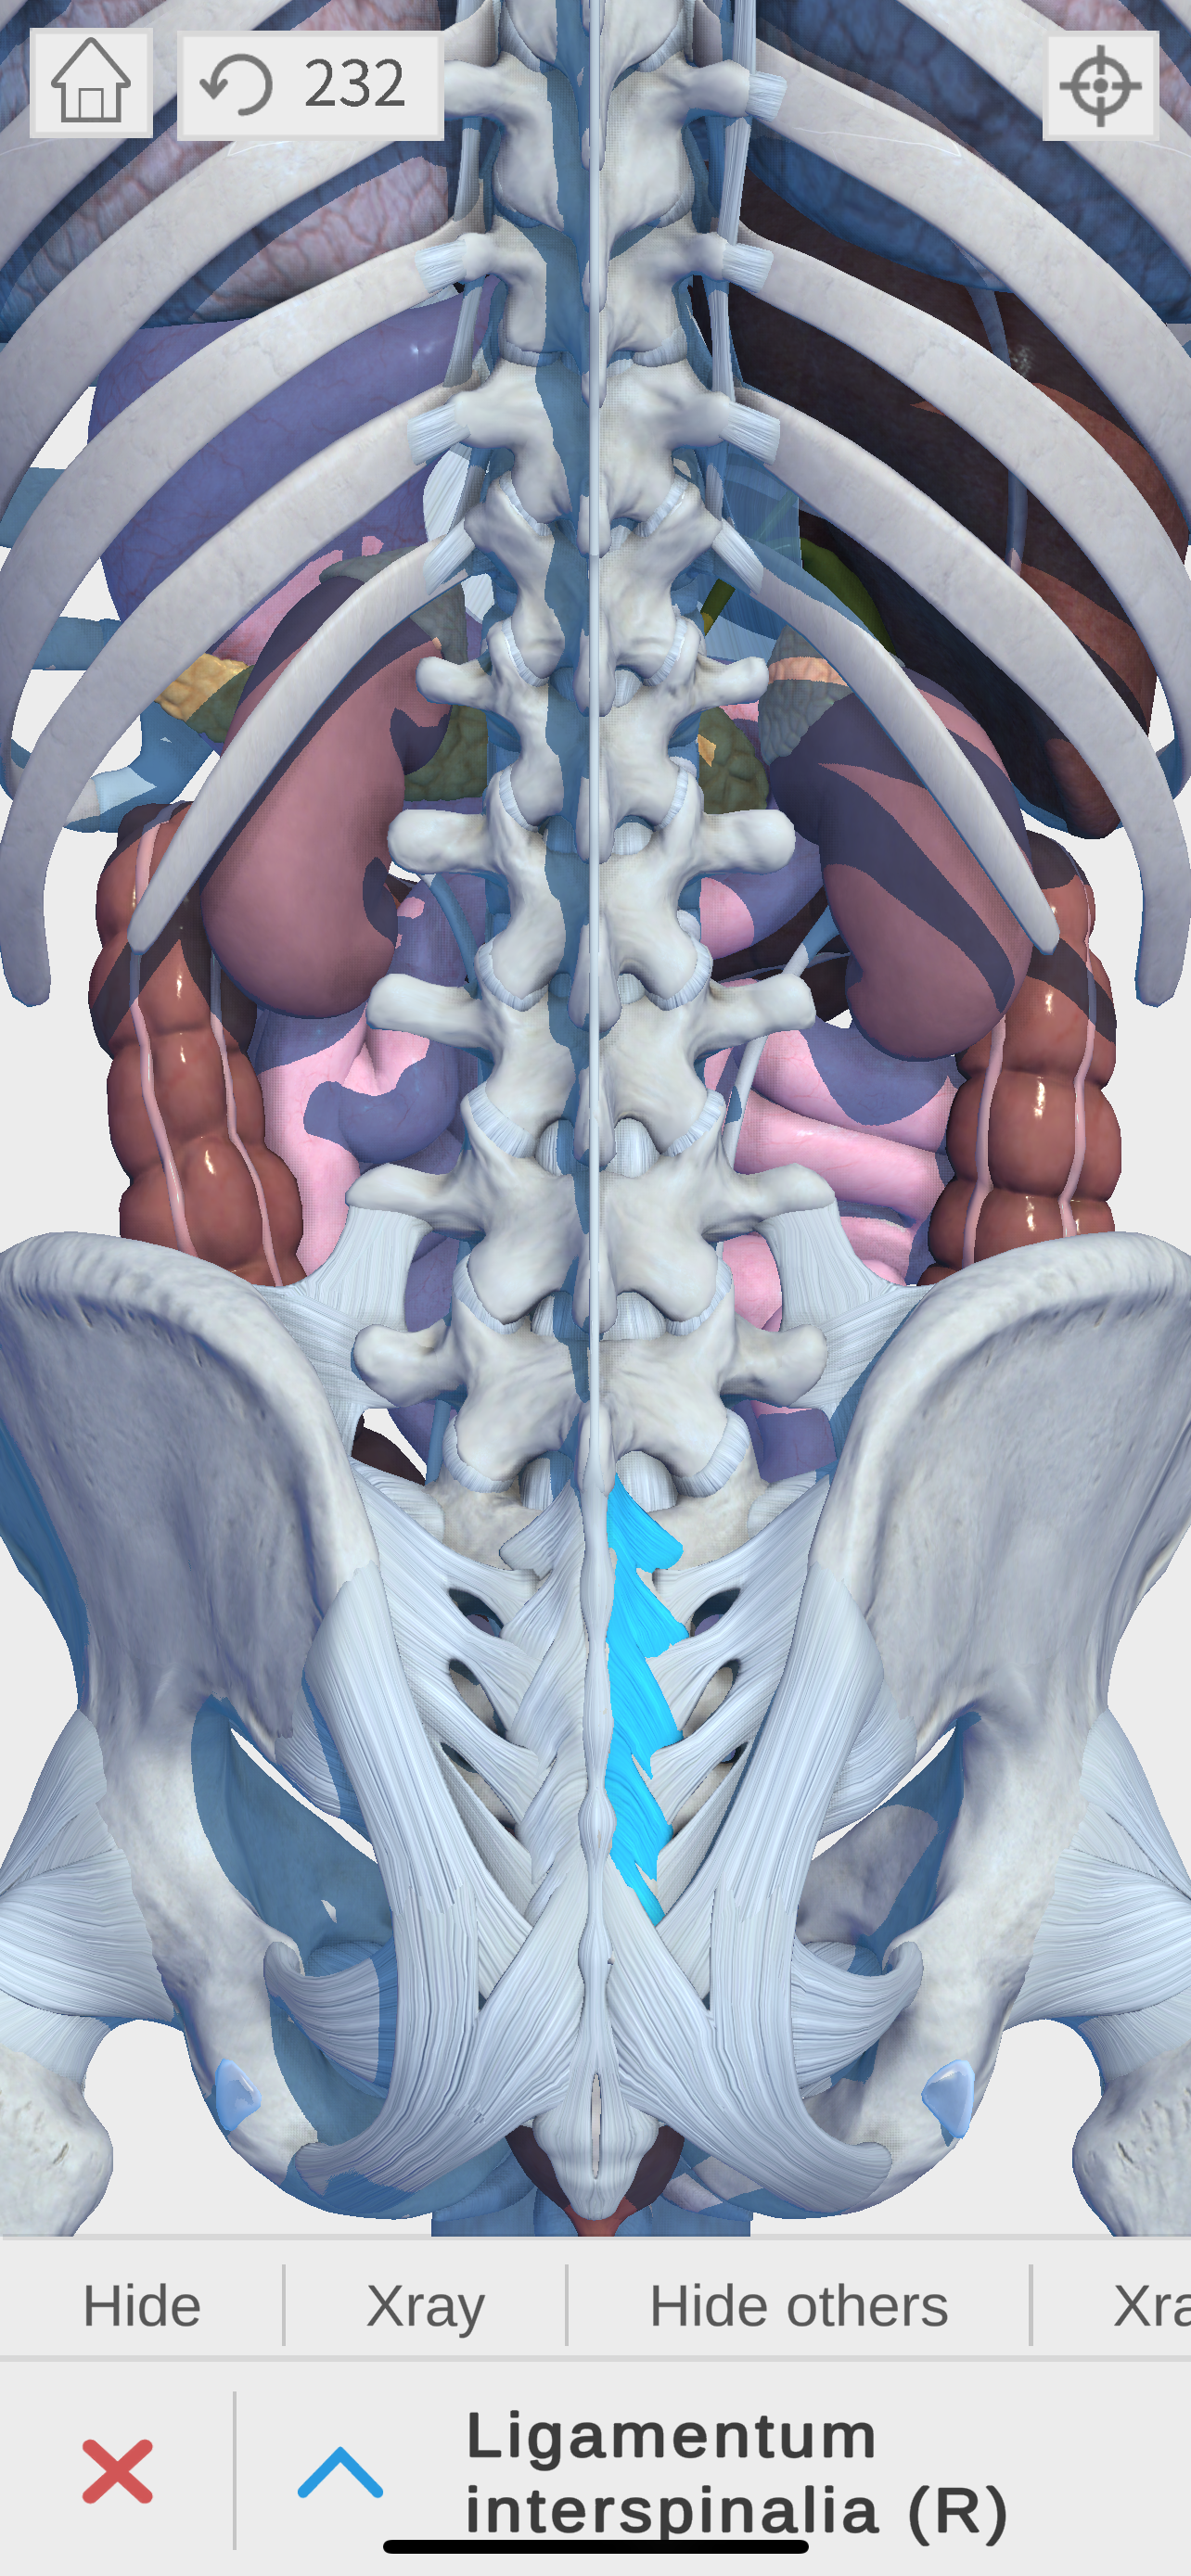

Complete and easy-to-use virtual guide for learning, understanding, and visualizing the complexities of human anatomy in 3D. Includes information and images for each anatomical system and part, multiple options to interact with the 3D anatomy models (hiding, fading, etc), and much more.

We believe that learning by interaction is the best and easiest way to study human anatomy.

- highly detailed

- zoom, pan, and rotate in real time

- show and hide layers

- see details for each body part

- Ligamentous